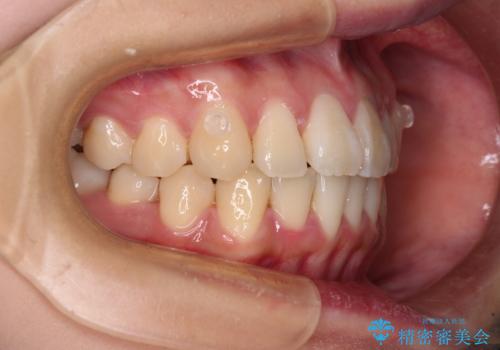

- 前歯の捻れを気にして来院された患者様です。

上顎前歯が捻れて前方に飛び出しており、下顎前歯もそれに沿うようにデコボコとなっていました。

IPR(歯と歯の間を削る処置)によりスペースを獲得して下顎前歯のデコボコを改善し、上顎前歯は下顎前歯と接する位置にまで引っ込めるように設定し、インビザラインにて矯正治療を行うこととしました。

しっかりと装着時間を守ってくださったので、予定通り1年強で治療を終えることができました。